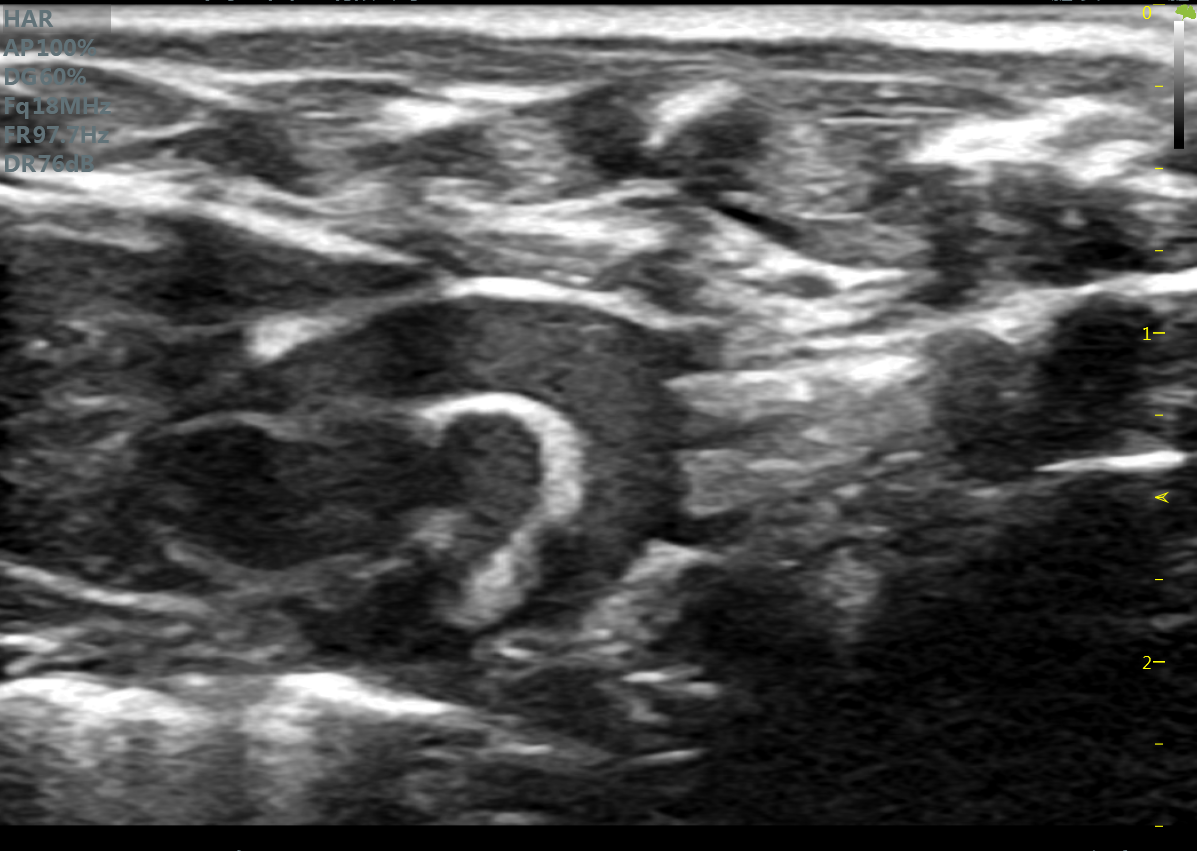

小鼠主动脉弓 小鼠肾脏血流

大鼠长轴B型 大鼠主动脉弓

大鼠胎鼠心脏血流 大鼠心尖四腔